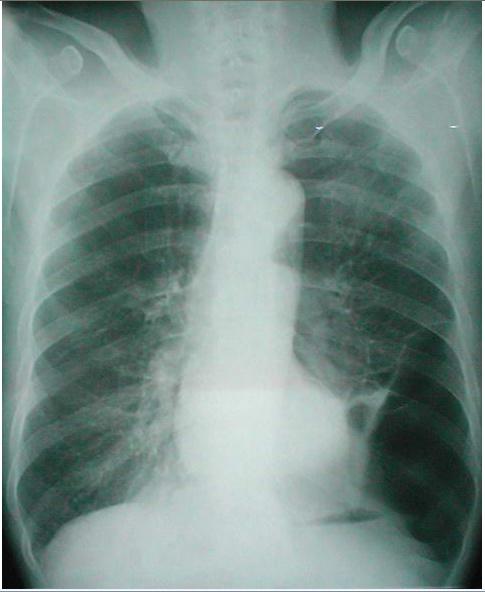

肺大泡x线表现图片,肺大泡x线

胸片:肺大疱 or 局限性肺气肿?

肺大泡的x线典型图片

肺大泡胸片

肺大泡x光胸片图像

肺大泡影像学表现图片